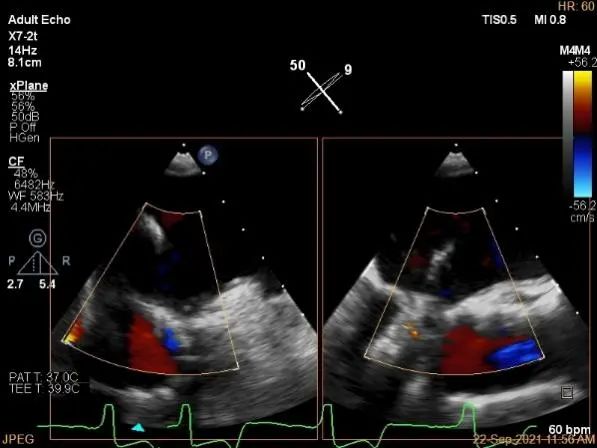

术中超声

麻醉状态下肺静脉血流频谱

房间隔穿刺点选择

穿刺高度:4.08cm

瓣叶捕获后,计算前叶捕获长度9mm,后叶捕获长度7mm。

夹子夹闭后,未见明确残余分流

肺静脉血流频谱恢复正常